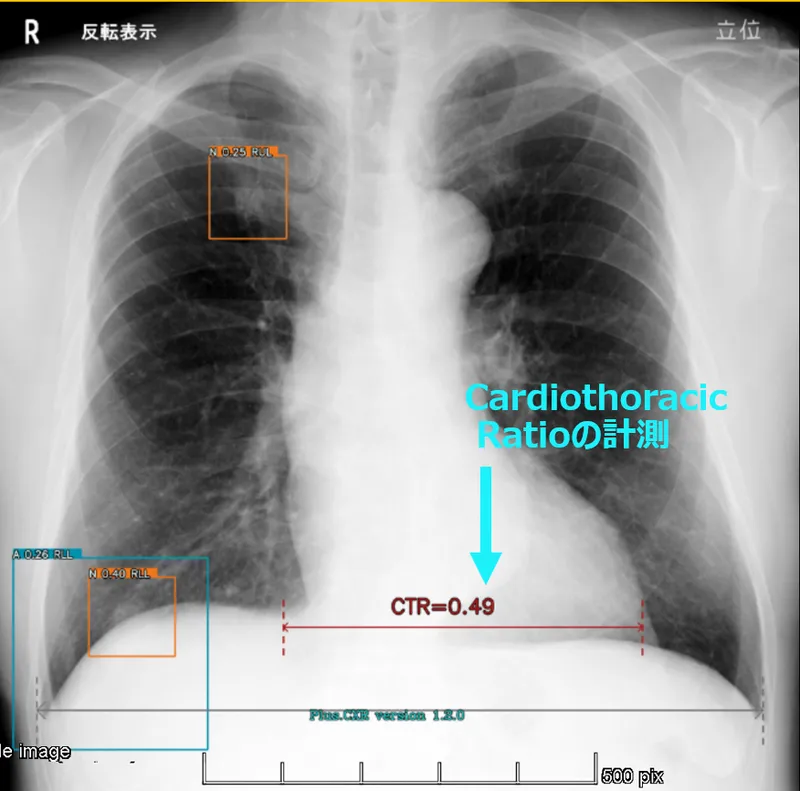

心臓や横隔膜と重なる部分も対象です AUC91~96% Cardio-Throacic Ratioを自動計測します